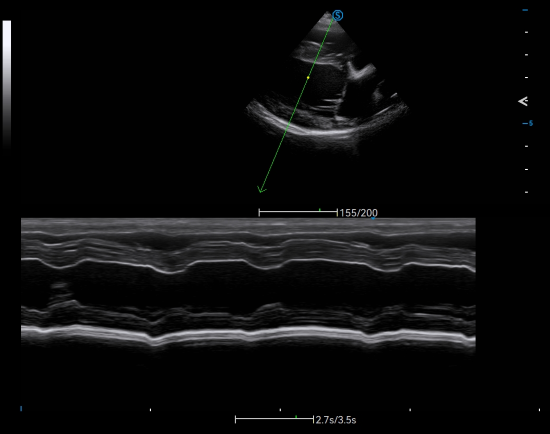

Cutting-edge Technologies Deliver Premium Images

● Pixel Echo Zone sensitively captures the rapid cardiac motion of animals at high frame rate through wide-band information processing.

Cardiology Applications

● AMM allows simultaneous assessment of cardiac wall motion for multiple sections, thereby facilitating efficient diagnosis of dilated cardiomyopathy for large-sized canines.